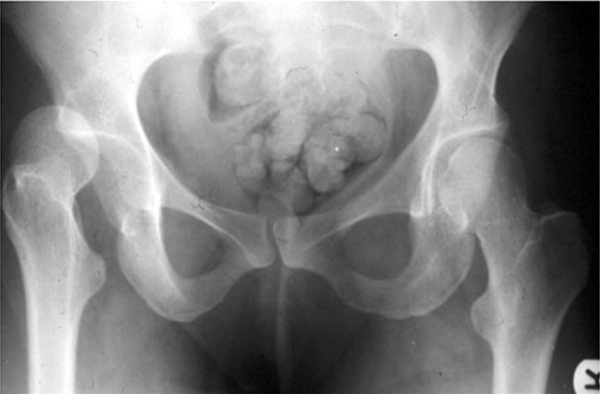

Hvordan stilles diagnosen?

Skadetypen, smerterne og hoftens stilling giver mistanke om tilstanden. Lægen på sygehuset vurderer muligheden for nerve- og karskade, da det kan ændre behandlingen.

Det er nødvendigt med røntgenundersøgelse og CT-skanning for at afklare, om der kan være komplicerede brud.

Der skelnes mellem to hovedtyper baseret på, hvor lårbenshovedet befinder sig efter ledskreddet:

• Lårbenshovedet kan forskydes ud til siden og bagover. Denne skade udgør 70-80 % af alle tilfælde, hvor hoften går ud af led, og 90 % af alle de tilfælde, der sker på grund af sport. I 10-30 % af tilfældene med lårbenshovedet forskudt bagover vil dette kunne skade iskiasnerven, som befinder sig lige bag hofteleddet. Ved denne skade er låret ofte bøjet i hoften og vender indover (krydser det andet lår) og roteret indad

• Lårbenshovedet kan forskydes forover, så det bliver liggende over kønsbenet. Låret står da vendt udover og roteret udad

Man kan stille diagnosen avaskulær nekrose ved røntgenundersøgelse fra få måneder til få år efter skaden. Ved tiltagende smerter fra hoften bør der tages røntgenbilleder, eventuelt MR-billede eller SPECT-CT-skanning for at undersøge for tegn på avaskulær nekrose.

Slidgigtforandringer i leddet - hofteledsartrose - er den hyppigste langtidskomplikation til hofteluksation og rammer op til 70 %. Man regner med, at slidgigten skyldes skaden på ledbrusken i skadeøjeblikket. Røntgen vil med tiden påvise slidgigtforandringerne. Det kan på længere sigt i så fald blive nødvendigt med udskiftning af hoften til en kunstig hofte.